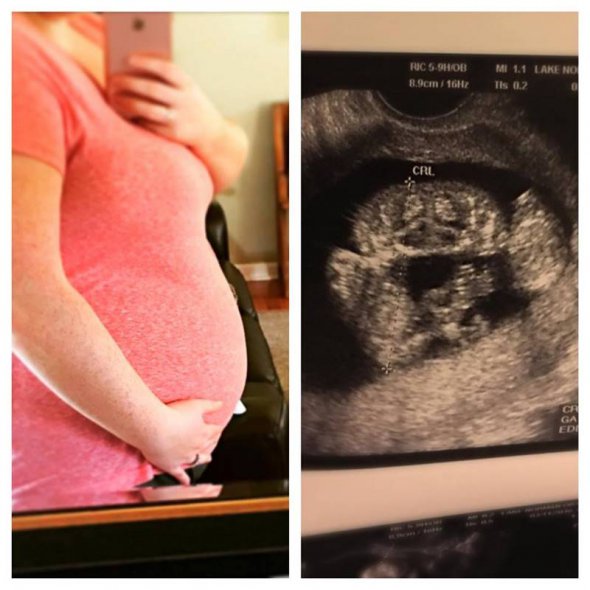

Батьки дівчат Хізер і Райлі ніколи не відмовлялися від своїх доньок. Вони дізналися про краніопагію майбутніх дітей на 11-му тижні вагітності і одразу почали вивчати спеціалізовану допологову допомогу. Дівчата народилися на 10 тижнів раніше терміну, за допомогою кесаревого розтину.